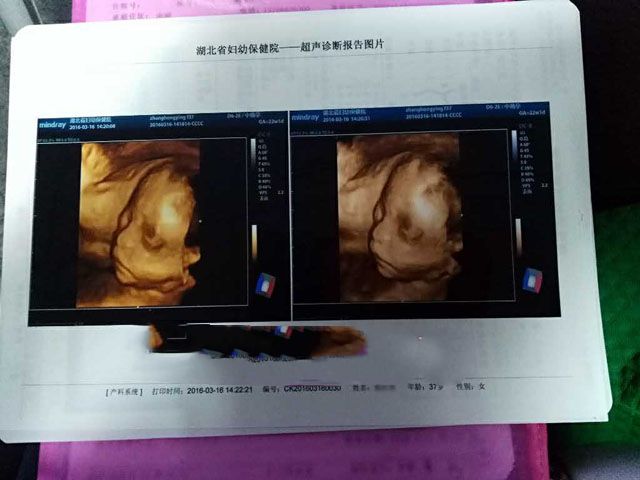

要不要看看产检记录!

2016年7月4日,孕37周,男宝宝顺利降临。